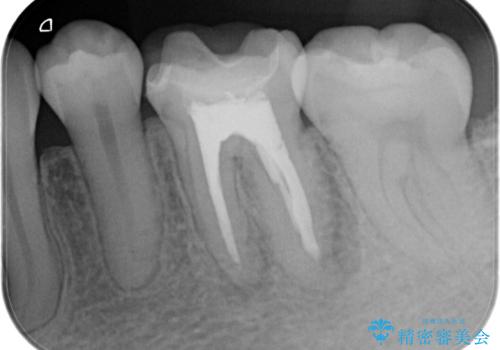

- 昔他院で根管治療を行った歯の病気が再発したことを主訴に来院されました。

レントゲンにて根尖に病変を認め、根尖性歯周炎の診断のもと以下の治療をご提案しました。

外科的歯内療法は根尖性歯周炎の治療における選択肢の一つです。

手術が必要ですが、通常の根管治療では解決できない解剖学的要因も解決できる可能性があります。